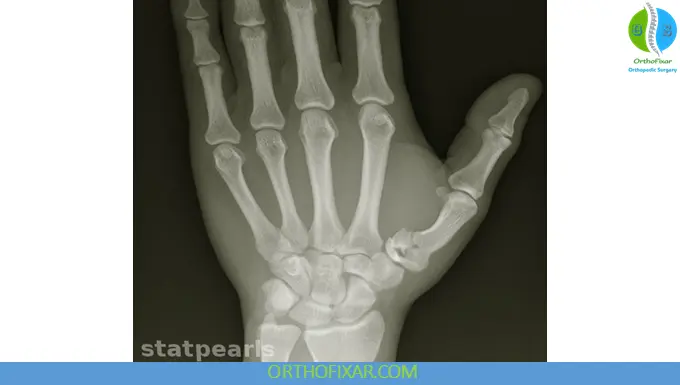

A Rolando fracture is a comminuted intra-articular fracture at the base of the first metacarpal (thumb). It typically presents with a “Y-shaped” or “T-shaped” fracture pattern, involving multiple fragments and extending into the carpometacarpal (CMC) joint.

Diagnosis

Imaging

- Plain radiographs (X-rays)

- AP, lateral, and oblique views

- CT scan (recommended)

- Provides detailed visualization of:

- Fragment number

- Articular involvement

- Surgical planning